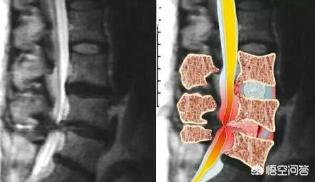

La pathogenèse de la hernie discale lombaire est due à la dégénérescence du disque intervertébral lombaire (composé du nucleus pulposus, de l'annulus fibrosus et de la plaque cartilagineuse), tandis que l'annulus fibrosus se rompt partiellement ou complètement et que le nucleus pulposus fait saillie pour irriter ou comprimer la racine nerveuse et la cauda equina, ce qui constitue un syndrome et une maladie dégénérative de la colonne vertébrale fréquente en clinique. Elle se manifeste principalement par des symptômes tels que des douleurs lombaires, une sciatique, un engourdissement des membres inférieurs et le syndrome de la cauda equina.

L'anneau fibreux est complètement rompu et le nucleus pulposus fait saillie dans le canal rachidien, mais le ligament longitudinal postérieur reste intact. La nécessité d'une intervention chirurgicale est déterminée par la gravité de la maladie.

Les hernies discales lombaires provoquent des symptômes de douleur du nerf sciatique le plus souvent associés à des lésions discales lombaires 3-sacrées 1, qui se produisent en raison de la pression exercée par la hernie discale lombaire sur la racine nerveuse.

La douleur du nerf sciatique causée par une hernie discale lombaire est principalement un symptôme nerveux du côté comprimé. Les symptômes sont évidents dans la zone d'innervation du nerf sciatique.

Le disque intervertébral est une structure fibreuse reliant deux vertèbres, composée d'un anneau fibreux périphérique et d'un noyau pulpeux au centre, riche en eau. La dégénérescence du disque intervertébral, les mauvaises postures, la position assise et debout prolongée, le froid, le froid et l'humidité, entraînent une détérioration de l'anneau fibreux périphérique du disque intervertébral, le noyau pulpeux au centre du disque intervertébral fait saillie et comprime la racine nerveuse. Manifestations cliniquesDes lombalgies, des douleurs irradiantes et un engourdissement des membres inférieurs, ainsi qu'une atrophie musculaire des membres inférieurs peuvent être présents à long terme. Si le nerf cauda equina est comprimé par la saillie, il se manifeste par un dysfonctionnement de la deuxième selle et un engourdissement du périnée.